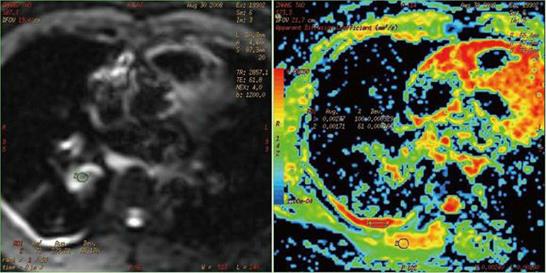

针对胸部的病变而言,CT对于肺组织和血管的分辨率均较好,磁共振对于血管的走行及其与周围组织关系的观察具有一定长处。在绝大部分情况下,CT对于肺部病变的观察已经足够,因此,除非特别需要观察血管构象关系等情况,否则较少使用磁共振来进行肺部的检查。

磁共振在反映病灶血供及血管方面具有一定特色